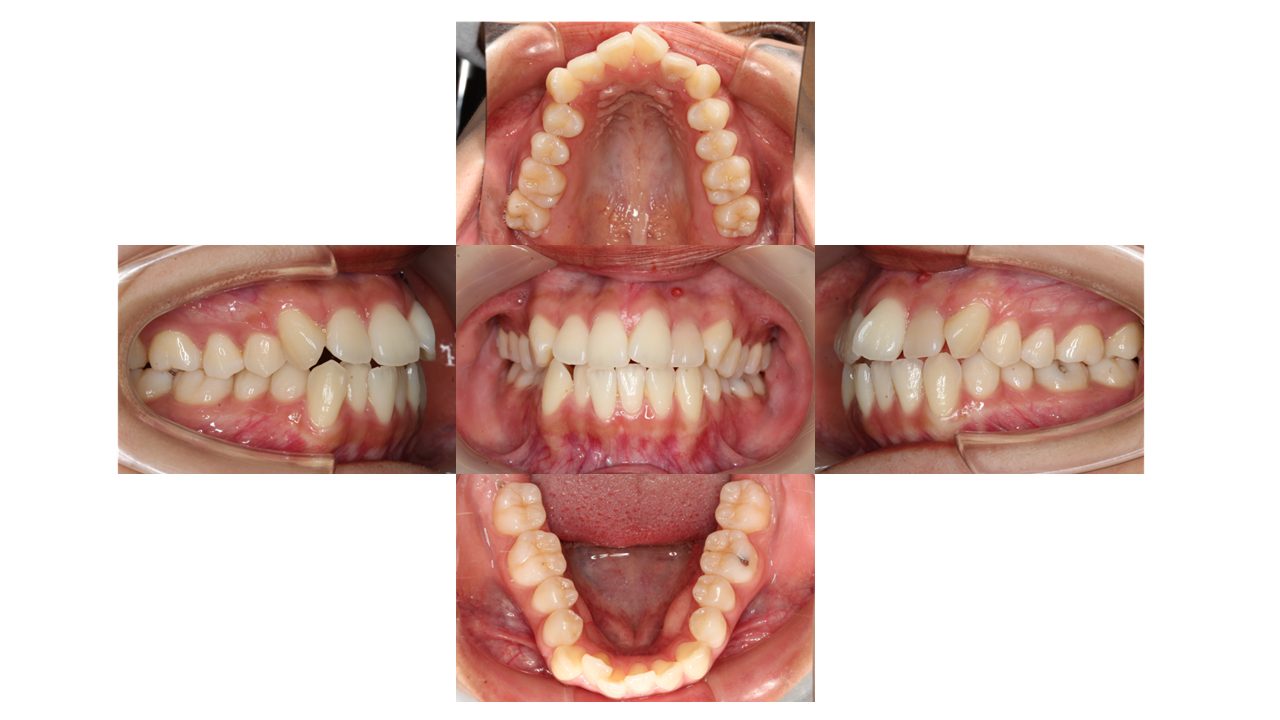

初診時の口腔内の状態です。

上下前歯の凸凹、特に上顎左右の3番目の箇所、そして下顎前歯の凸凹にお悩みでご来院されました。